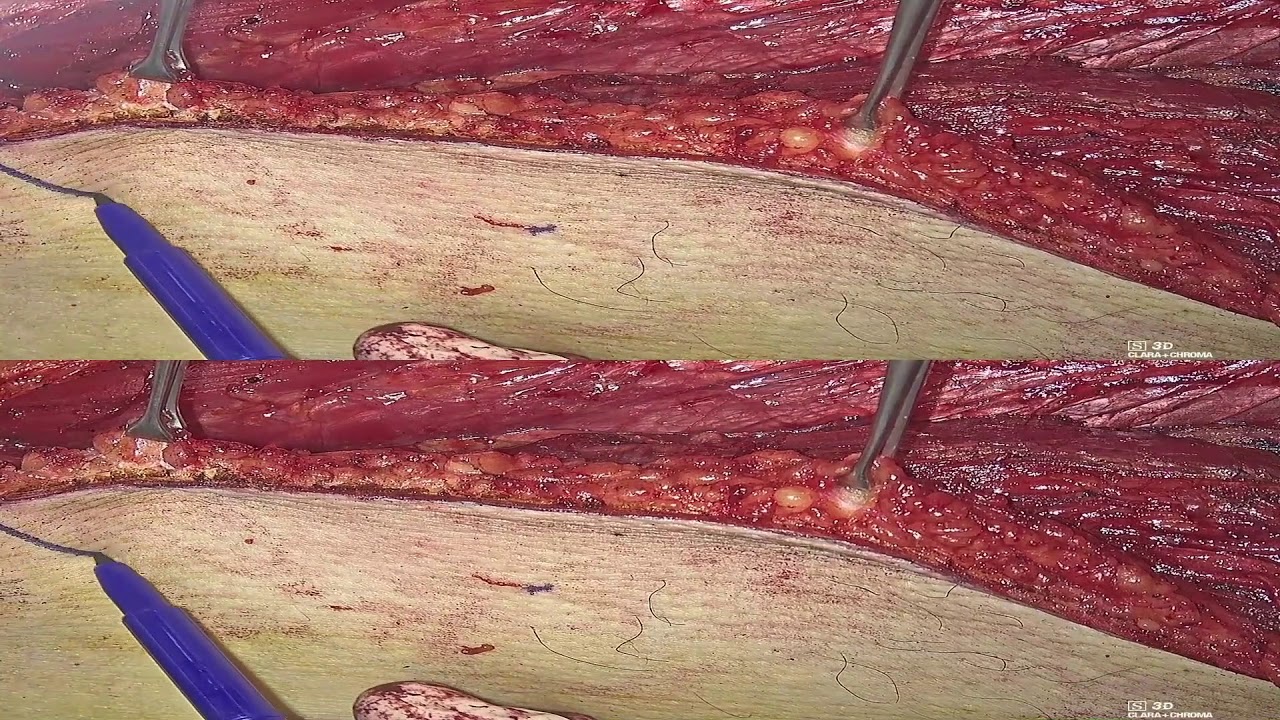

- Chirurgia Robotica

- Sviluppo di nuove tecniche chirurgiche mini-invasive per la regione testa-collo

- Chirurgia Robotica